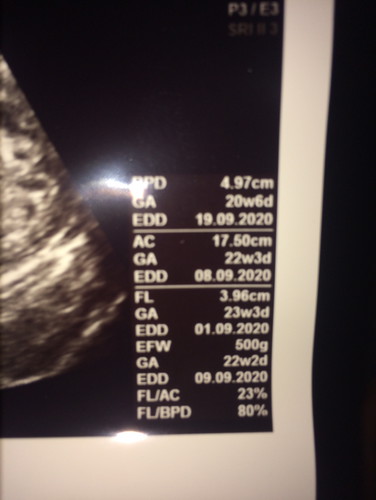

ในนี่เขียนบอกอายุครรภ์เท่าไร ตอนนี้เรา23+2 รพ.บอกกำหนดคลอด5กย.ไปซาวดูเพศที่คลินิกมาบอกว่ากำหนดคลอด9กย. ท้องเเรก

GA ด้านบน 20w 6d ค่ะ EDD เป็นกำหนดคลอดชั่วคราวเท่านั้นค่ะ EDC ถึงกำหนดคลอดจริง